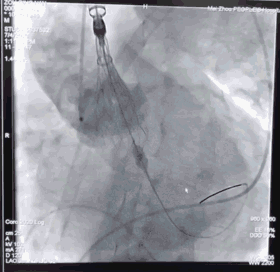

植入VitaFlow TAV 27的瓣膜,进行定位释放

瓣膜释放完成,封堵效果良好

3228-200胸主动脉支架定位

胸主动脉支架释放后造影